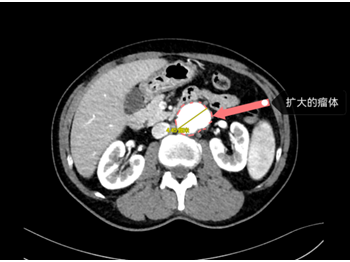

主动脉CT血管造影检查结果是

腹主动脉夹层动脉瘤

直径已达到4.45厘米

图片